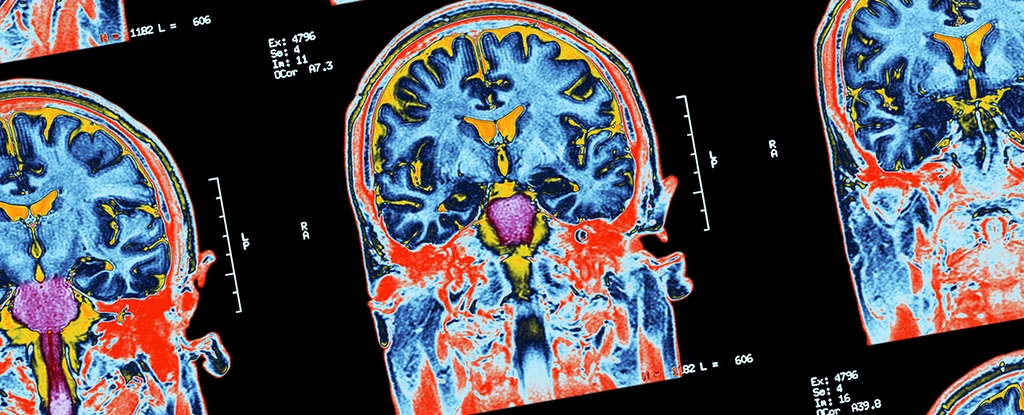

Up to one in four patients who are unresponsive after suffering serious brain injuries might actually still be conscious – indicating more patients may be aware of their surroundings than previously realized, new research suggests.

This state of 'hidden consciousness' is now officially known as cognitive motor dissociation (CMD), where cognitive (or thinking) abilities aren't connected to motor (or movement) abilities. Researchers have been looking into CMD for several years.

However, 62 percent of an additional 112 patients who were visibly responding to instructions at the bedside didn't exhibit the expected brain signals showing responsiveness – so the researchers suggest their methods still don't detect everyone with cognitive function.